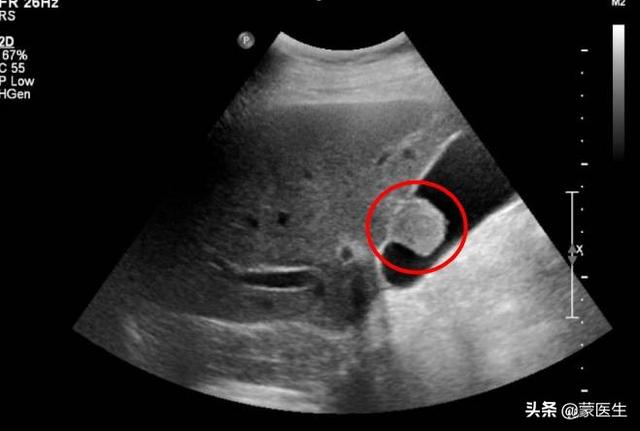

胆嚢ポリープ

赤い丸は胆嚢ポリープ。

胆嚢ポリープは真性ポリープと偽性ポリープに分けられる。偽ポリープはコレステロールポリープとも呼ばれ、集団で発生することが多く、直径は1cm以下で、コレステロールの結晶のみで、基本的に悪性の可能性はありません。

そして、真のポリープには、胆嚢腺腫、腺筋腫、炎症性ポリープ、腺腫性過形成の4つのカテゴリーがあり、その中でも胆嚢腺腫が最も危険で、胆嚢ポリープの発生率は約4%に過ぎないが、発がん率は約20~30%で、通常は単独で戦うのが好きである。

なぜ胆嚢ポリープができるのですか?

一般的な原因因子としては、鍋物、焼肉、卵黄、動物の内臓肉などの脂っこい食事を好むこと、朝食抜きや飢餓状態などの不規則な食生活、夜更かしの頻発や不規則な生活習慣、家系的な遺伝などが挙げられる。

40歳以上の人には年1回の腹部超音波検診が推奨される。ハイリスク因子がなく、ポリープが1cm未満で、50歳未満の患者は、3~6ヶ月に1回超音波検査を受け、その結果が良好であれば、超音波検査を年1回に変更することができる。